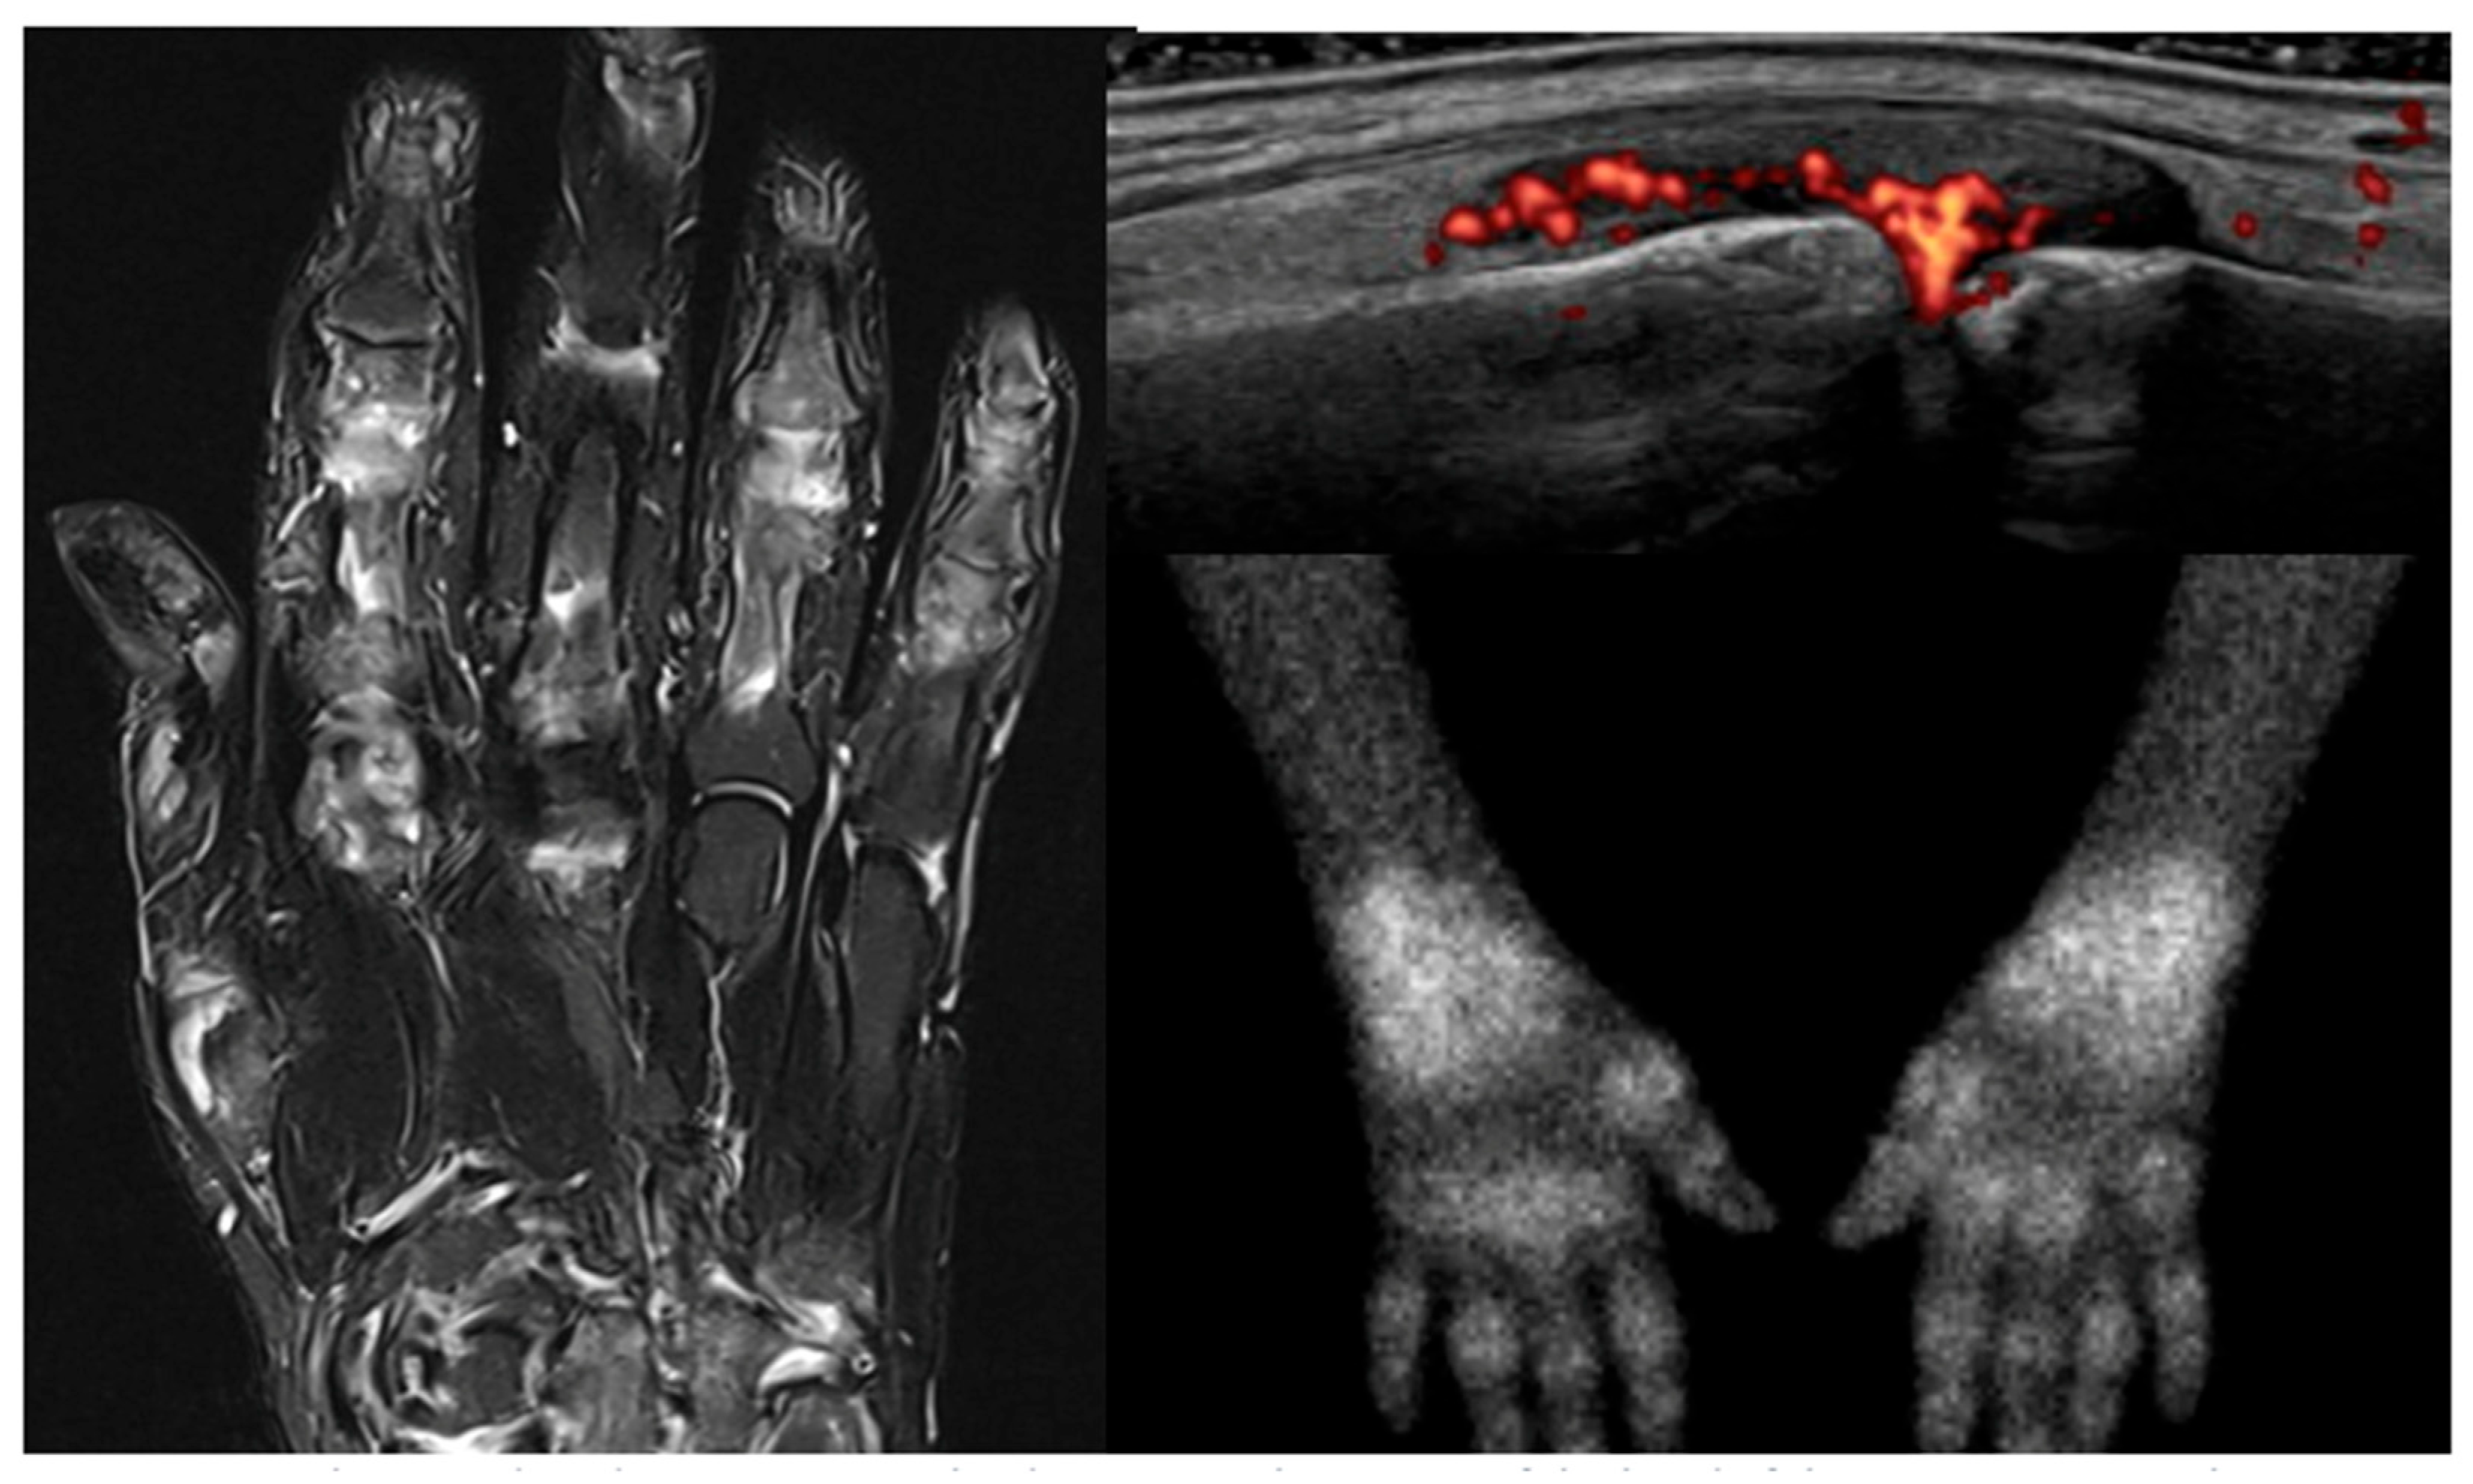

- Miese, F.; Scherer, A.; Ostendorf, B.; Heinzel, A.; Lanzman, R.S.; Kröpil, P.; Blondin, D.; Hautzel, H.; Wittsack, H.-J.; Schneider, M.; et al. Hybrid 18F-FDG PET-MRI of the hand in rheumatoid arthritis: Initial results. Clin. Rheumatol. 2011, 30, 1247–1250. [Google Scholar] [CrossRef]

- Roimicher, L.; Lopes, F.P.P.L.; de Souza, S.A.L.; Mendes, L.F.; Domingues, R.C.; da Fonseca, L.M.B.; Gutfilen, B. 99mTc-anti-TNF-α scintigraphy in RA: A comparison pilot study with MRI and clinical examination. Rheumatology 2011, 50, 2044–2050. [Google Scholar] [CrossRef]